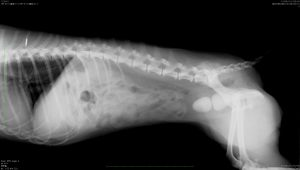

★膀胱結石のレントゲン写真★ 骨盤の前におにぎり型の結石が2つ認められます

上記の膀胱結石は、レントゲンの子から摘出したものです。こちらは「ストルバイト結石」です。